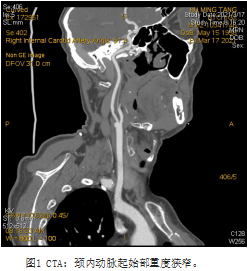

北京清华长庚医院4月28日电(通讯员 赵克强 吴巍巍)胡先生,62岁,3月前无明显诱因出现左手麻木、无力,5分钟后自行缓解,超声发现右颈动脉起始部狭窄70%,就诊于清华长庚医院血管外科。入院后完善术前检查,赵克强副主任医师为患者行全脑动脉造影提示:右侧颈动脉重度狭窄,颈总动脉巨大溃疡型斑块,延迟可见造影剂滞留于溃疡内;斑块超声造影及高分辨核磁分析,评估为不稳定斑块,极易脱落导致脑梗死。头颅MR可见脑内陈旧性多发腔隙性梗塞灶,以右侧前循环供血区域为著;患者原本计划行颈动脉支架微创手术,但考虑到支架无法完全覆盖巨大溃疡,围术期梗死风险较大,不适宜实施该项手术,经全科讨论后决定为患者进行颈动脉内膜剥脱术,血管外科吴巍巍主任、赵克强副主任医师在全麻下为老胡安全实施颈动脉内膜剥脱术,术后病理提示颈动脉巨大溃疡型斑块,斑块内出血;术后48小时顺利拔除伤口引流,1周拆线、康复出院,术后随访期间未再次出现TIA发作。